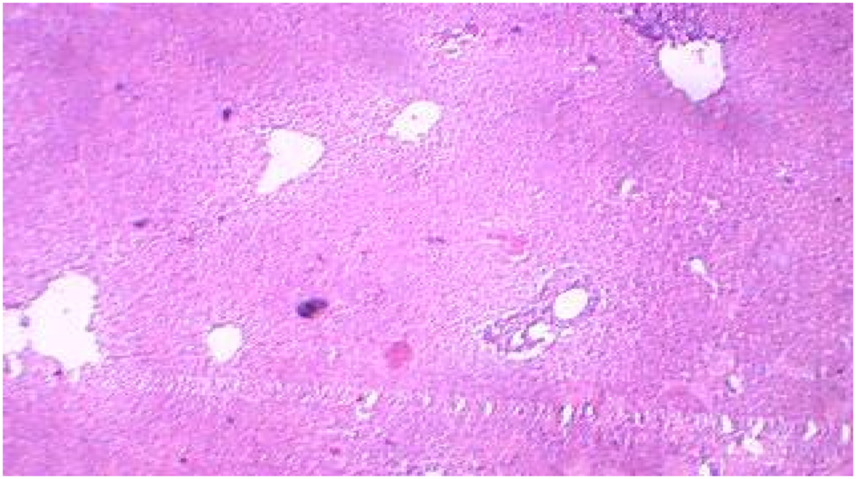

Liver

The histopathological sections of control and treated livers showed marked variations, as represented in Figures 4, 5. The sections of the treated livers showed liver necrosis, which may be due to the direct toxic effects of pollutants on hepatocytes since the liver is the main site of detoxification for all types of toxins and chemicals. Oxygen deficiency because of gill degeneration may be the common cause of cellular degeneration in the liver. The vascular dilation, intracellular hemolysis, and thrombosis formation observed in blood vessels, with subsequent stasis of blood, may also be responsible for cellular degeneration and necrosis in the liver. Histopathological tests in the livers of carp exposed to hexachlorocyclohexane have revealed diffuse necrosis, just as in the present case (Monteiro et al., 2006). These findings suggest that DCM and other chlorine-containing compounds have similar effects on the liver.

FIGURE 4

Control liver showing preserved architecture.

FIGURE 5

Treated liver showing necrosis.